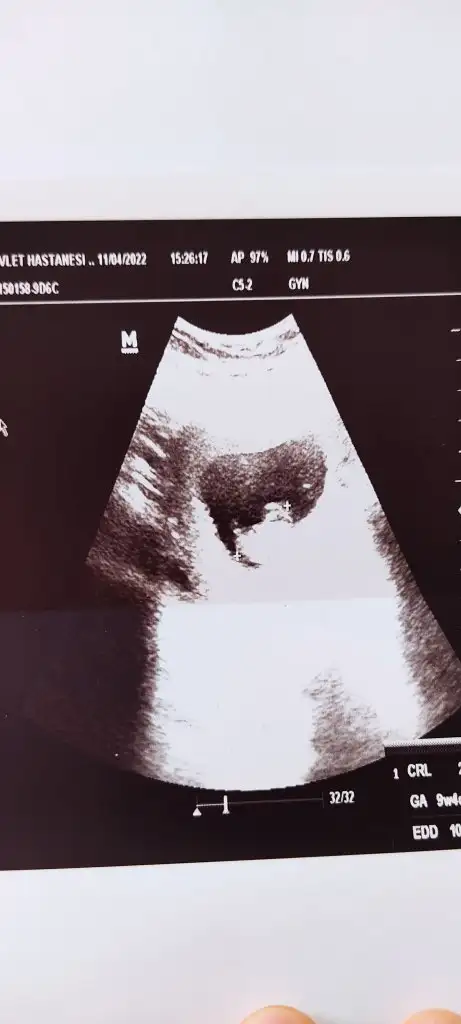

Slm canım nasılsın bakalım 🥰 9+1 deyiz tekrar bakıp yorumlayabilir misin rica etsem 🥰

• IMG_20220412_155700.webp

IMG_20220412_155700.webp

17,8 KB · Görüntüleme: 69

• IMG_20220412_155652.webp

IMG_20220412_155652.webp

17,3 KB · Görüntüleme: 66

Sana önceden ne dedim. kuzum bilmiyorum ama burda kız görünüyor

6 buçuk haftalık tık erkek demiştin kuzum şuan 9 haftamdayım Allah'ın izniyle sağlıklı olsun evlatlarımız gerisi önemli değil eşim kız istiyor ben erkek istiyorum bakalım hayırlısı olsun 🙏 dur eskisinide atiyim hatta şimdi ikisini karşılaştır istersen 🥰

senin 6. hafta görüntüsü vajinal mı kuzum eğer vajinalsa iki görüntüde kız diyor eğer değilse benim gibi bebek yer değiştirmiş